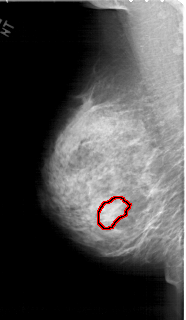

A_1453_1.LEFT_CC

LEFT_CC LINES 6421 PIXELS_PER_LINE 3391 BITS_PER_PIXEL 12 RESOLUTION 43.5 OVERLAY

FILE: A_1453_1.LEFT_CC.OVERLAY

TOTAL_ABNORMALITIES 1

ABNORMALITY 1

LESION_TYPE MASS SHAPE LOBULATED MARGINS OBSCURED

ASSESSMENT 4

SUBTLETY 2

PATHOLOGY BENIGN

TOTAL_OUTLINES 1

BOUNDARY